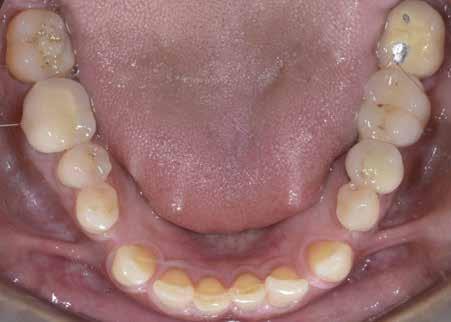

A felnőtt páciensek kezelése során általában egyszerre több ellátásra szoruló elváltozást is diagnosztizálhatunk: hiányzó fogak, kopott fogazat, esetleg régi, nem megfelelő, sérült fogpótlások, rendellenes helyzetben lévő fogak stb… Ezen páciensek kezelésekkel kapcsolatos kérései mindig az esztétikai vagy a rágással kapcsolatos kívánságaik kielégítését szolgálja. A kezelések során a fogorvosoknak nem csak a páciensek kéréseinek teljesítésére, hanem ezzel egyidejűleg a fogazat általános megjelenésének és funkciójának lehetőség szerinti javítására is törekedniük kell. Mindemellett a lehető legtöbb saját foganyag megőrzését és az évek során elvesztett kemény- és lágyrészek pótlását (pl.: hiányzó fogak, sorvadt állcsontgerinc, lágyszöveti defektusok) is szem előtt kell tartaniuk, úgy, hogy közben egy hosszú távon fenntartható eredményekkel járó kezelési tervet állítanak össze. Ezek mindig összetett esetek. Annak érdekében, hogy a fentiekben megfogalmazott összes kezelési célt teljesíteni tudjuk, interdiszciplináris megközelítésre van szükség. Az ilyen komplex rehabilitációs kezeléseket „fogászati megfiatalításnak” nevezzük. Ezeknek a beavatkozásoknak lényege az elhasználódott fogazat biológiai szempontokat figyelembe vevő minimál invazív módon történő helyreállításában rejlik, mely folyamat végére a páciensek fogai visszanyerhetik fiatalkori megjelenésüket.

A rehabilitációs kezeléseknek a célja, hogy a páciensek a lehető leghosszabb időn keresztül képesek legyenek mosolyogni és rágni. A protetikai kezeléseket végző fogorvosoknak helyre kell tudni állítaniuk a fogívek szabályos lefutását és az alsó és felső fogív között megfelelő interokkluzális érintkezéseket kell létrehozniuk. Így lehet csak az ellátás befejezését követően elért végeredmény biológiai szempontokat figyelembe vevő esztétikáját, funkcionális megfelelőségét, hosszú távú fenntarthatóságát biztosítani.